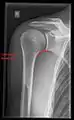

Imaging

Imaging of the shoulder includes ultrasound, X-ray and MRI, and is guided by the suspected diagnosis and presenting symptoms.

Conventional x-rays and ultrasonography are the primary tools used to confirm a diagnosis of injuries sustained to the rotator cuff. For extended clinical questions, imaging through Magnetic Resonance with or without intraarticular contrast agent is indicated.

Hodler et al. recommend starting scanning with conventional x-rays taken from at least two planes, since this method gives a wide first impression and even has the chance of exposing any frequent shoulder pathologies, i.e., decompensated rotator cuff tears, tendinitis calcarea, dislocations, fractures, usures, and/or osteophytes. Furthermore, x-rays are required for the planning of an optimal CT or MR image.[23]

The conventional invasive arthrography is nowadays being replaced by the non-invasive MRI and ultrasound, and is used as an imaging reserve for patients who are contraindicated for MRI, for example pacemaker-carriers with an unclear and unsure ultrasonography.[24]

X-ray

Projectional radiography views of the shoulder include:

CR. shoulay film.

Transaxillary conventional radiography

Y-projection conventional radiography